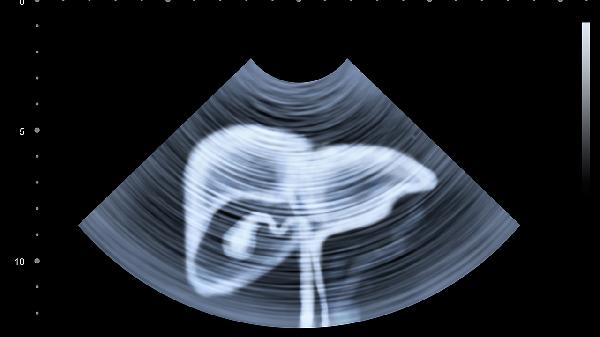

定期监测是确保治疗效果的关键。患者需定期进行肝功能、病毒载量等检查,评估治疗效果和病情进展。通过监测,医生可以及时调整治疗方案,确保治疗的有效性和安全性。长期随访也有助于早期发现并处理可能的复发或并发症。